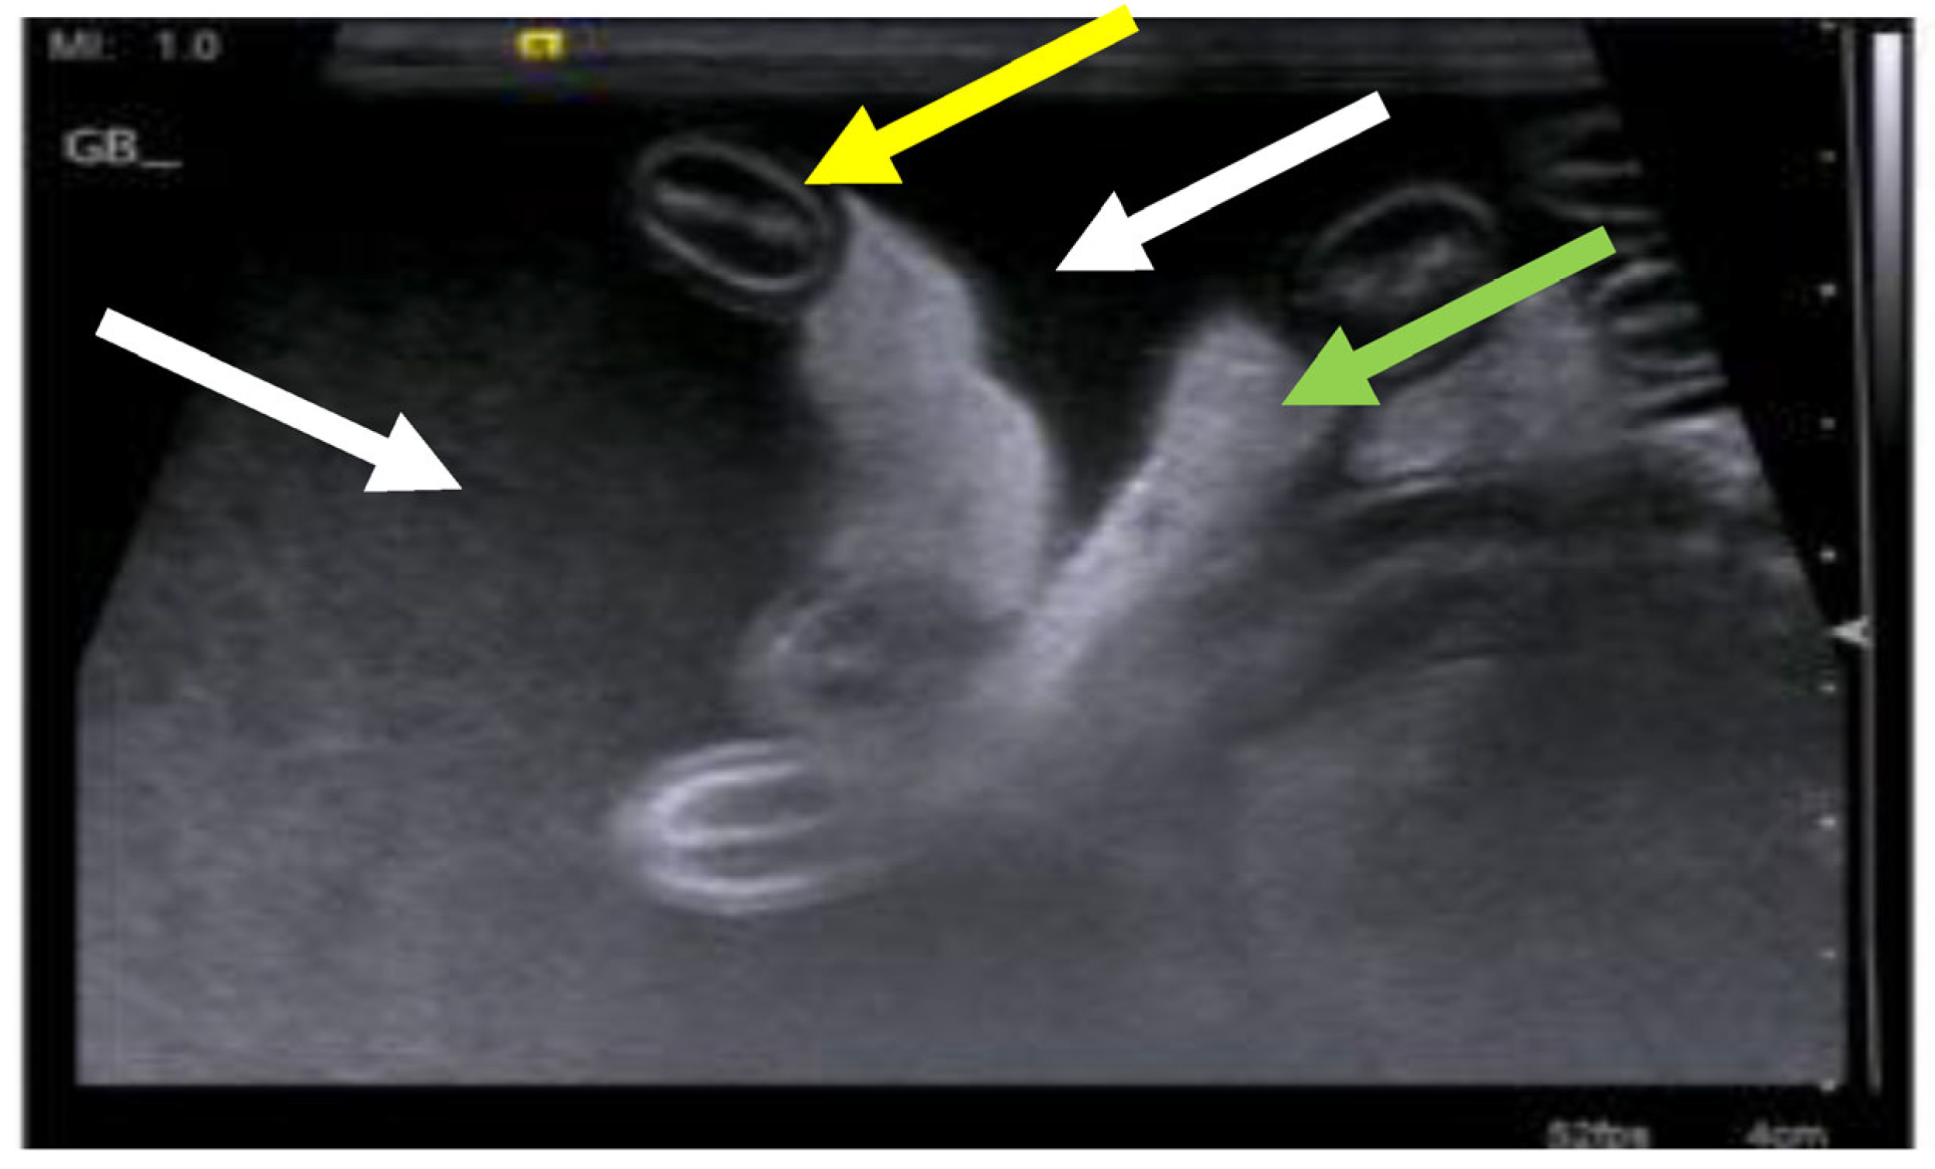

7.4. Diagnostic Imaging in FIP

7.4.1. Routine Imaging: Ultrasonographic and Radiographic Findings

| Summary of Section 7: Diagnosis of FIP; Section 7.4: Diagnostic imaging in FIP: No specific ultrasonographic or radiographic findings exist for FIP. Ultrasonography (in particular) and radiography can show the presence of effusions. Pneumonia due to FIP that is occasionally reported can be associated with radiographic changes. Ultrasonography can reveal abdominal lymphadenomegaly or lymphadenopathy and/or abnormalities of the liver, spleen, intestines and/or kidneys (which can include a medullary rim sign), depending on which organs are affected. Imaging can also be of use to the direct sampling of abnormal tissues, e.g., fine-needle aspirate for cytology examination to reveal non-septic pyogranulomatous inflammation, or ultrasound-guided needle core (e.g., tru-cut) biopsies can be collected and submitted for histopathology. When a cat is showing neurological signs, the imaging of the brain by magnetic resonance imaging, if available, with contrast, can be useful to demonstrate neurological abnormalities (such as obstructive hydrocephalus, syringomyelia, foramen magnum herniation and marked contrast enhancement of the meninges, third ventricle, mesencephalic aqueduct, and brainstem). A description of computerised tomography findings in cats with neurological FIP has not been published, but MRI is likely to be more sensitive in the detection of subtle intraparenchymal lesions. Advanced imaging of the central nervous system is indicated before performing cerebrospinal fluid sampling to assess the potential risk of herniation. |